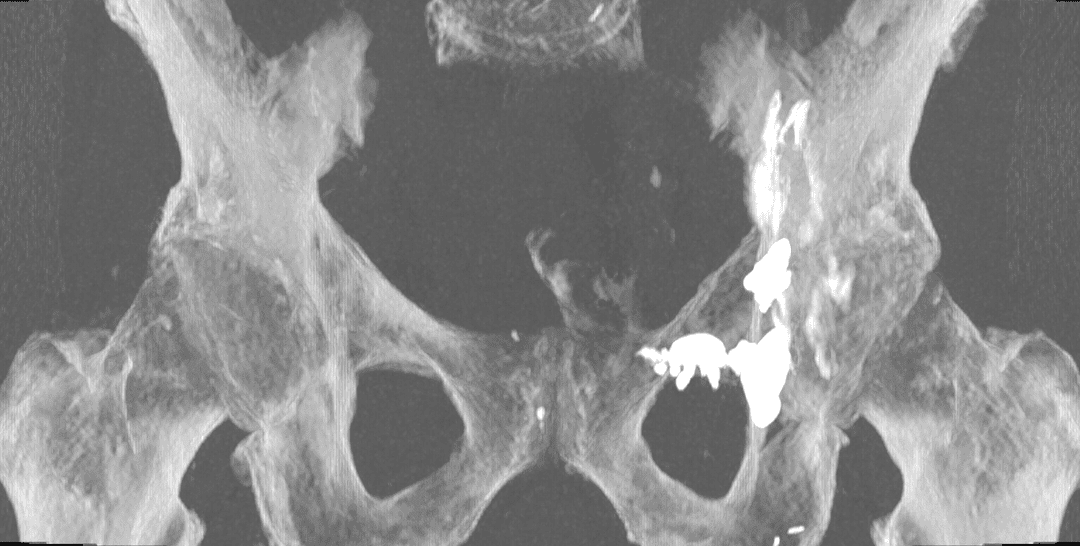

Fixation d'une fracture cotyloïdienne scanoguidée

Les fractures du toit du cotyle représentent un défi majeur en traumatologie orthopédique en raison de leur localisation dans une zone de charge et de leur proximité avec les structures articulaires. Traditionnellement traitées par des techniques chirurgicales ouvertes, ces fractures peuvent désormais bénéficier d’une approche mini-invasive grâce à l’ostéosynthèse sous guidage scanner. Le vissage percutané, réalisé sous imagerie CT, permet d’obtenir une réduction anatomique et une stabilisation précise des fragments osseux.

Analyse des images CT pour définir la trajectoire optimale du vissage en fonction du schéma de fracture.

Déterminer des repères anatomiques et la configuration osseuse pour minimiser le risque de pénétration intra-articulaire.